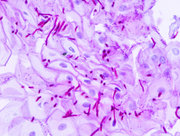

عدوى مجرى الدم (أو الإنتان الجرثومي) هو وجود جراثيم في الدم [2] والتي قد تكون عابرة ودون أعراض.[4] ووفقاً لمراكز مكافحة الأمراض واتقائها (CDC)، يمكن تعريف عدوى مجرى الدم بانها وجود بكتيريا قادرة على البقاء في الدم (أي تجرثم الدم) ومثبتة باستنبات دم (en) إيجابي.[5] يتم الكشف عن البكتيريا في الدم باستنبات الدم. وعادة ما يقصد بالإنتان البكتيري بوجود بكتيريا حية قادرة على البقاء في مجرى الدم.

الإنتان البكتيري أو تجرثم الدم هو وجود بكتيريا في الدم. ويتم الكشف عن البكتيريا في الدم باستنبات الدم. تجرثم الدم هو وجود البكتيريا قادرة على البقاء في مجرى الدم.